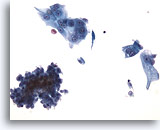

Figure 44

Voided urine, low grade carcinoma

The clusters in low grade urothelial carcinoma may or may not be papillary. 40x

Figure 44

Voided urine, low grade carcinoma

The clusters in low grade urothelial carcinoma may or may not be papillary.

40x

Voided urine, low grade carcinoma

The clusters in low grade urothelial carcinoma may or may not be papillary.

40x